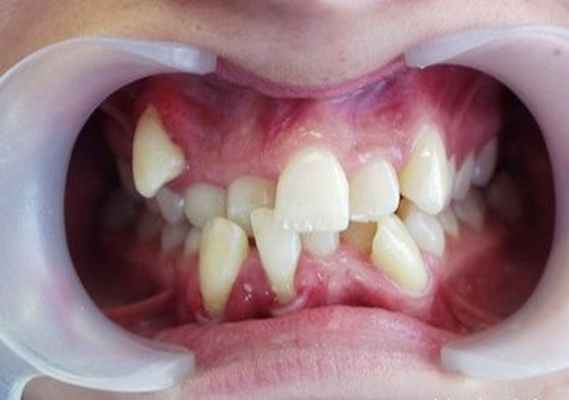

Рис. 3. Недостаток места в зубном ряду, тесное положение зубов у пациентки 15 лет

Мои зубы в 16 лет. На фото видно уже почти почти сформировавшиеся сверхкомплектные четверки и уже кривые зубы снизу

Из-за зубов мудрости резцы снизу скучились, и вообще все это удовольствие это прелюдия для исправления прикуса (но об этом как-то потом);

Постоянные зубы полиодонтия поражает чаще, чем молочные. У взрослого человека обычно появляются дистопированные и ретинированные сверхкомплектные зубы.

Дистопированными называют зубы, которые появляются за пределами зубной дуги. Наиболее часто они прорезываются на лингвальной поверхности десен и в области неба. При такой форме заболевания для больного характерно:

- плохое произношение звуков;

- заметное нарушение прикуса;

- изменение обычного расположения зубов: искривление угла, под которым они растут, а также их поворот

- вокруг своей оси;

- частое травмирование слизистой оболочки рта и как следствие ее воспаление;

- нарушение жевательных процессов, вследствие чего появляются проблемы с пищеварением.

Кроме всего прочего, дистопированные зубы часто становятся причинами психологических проблем. Из-за не эстетической, а порой совсем непривлекательной улыбки, больной становится замкнутым и малообщительным. Психологические проблемы, в свою очередь, вызывают хронические заболевания эндокринной, пищеварительной и нервной системы.